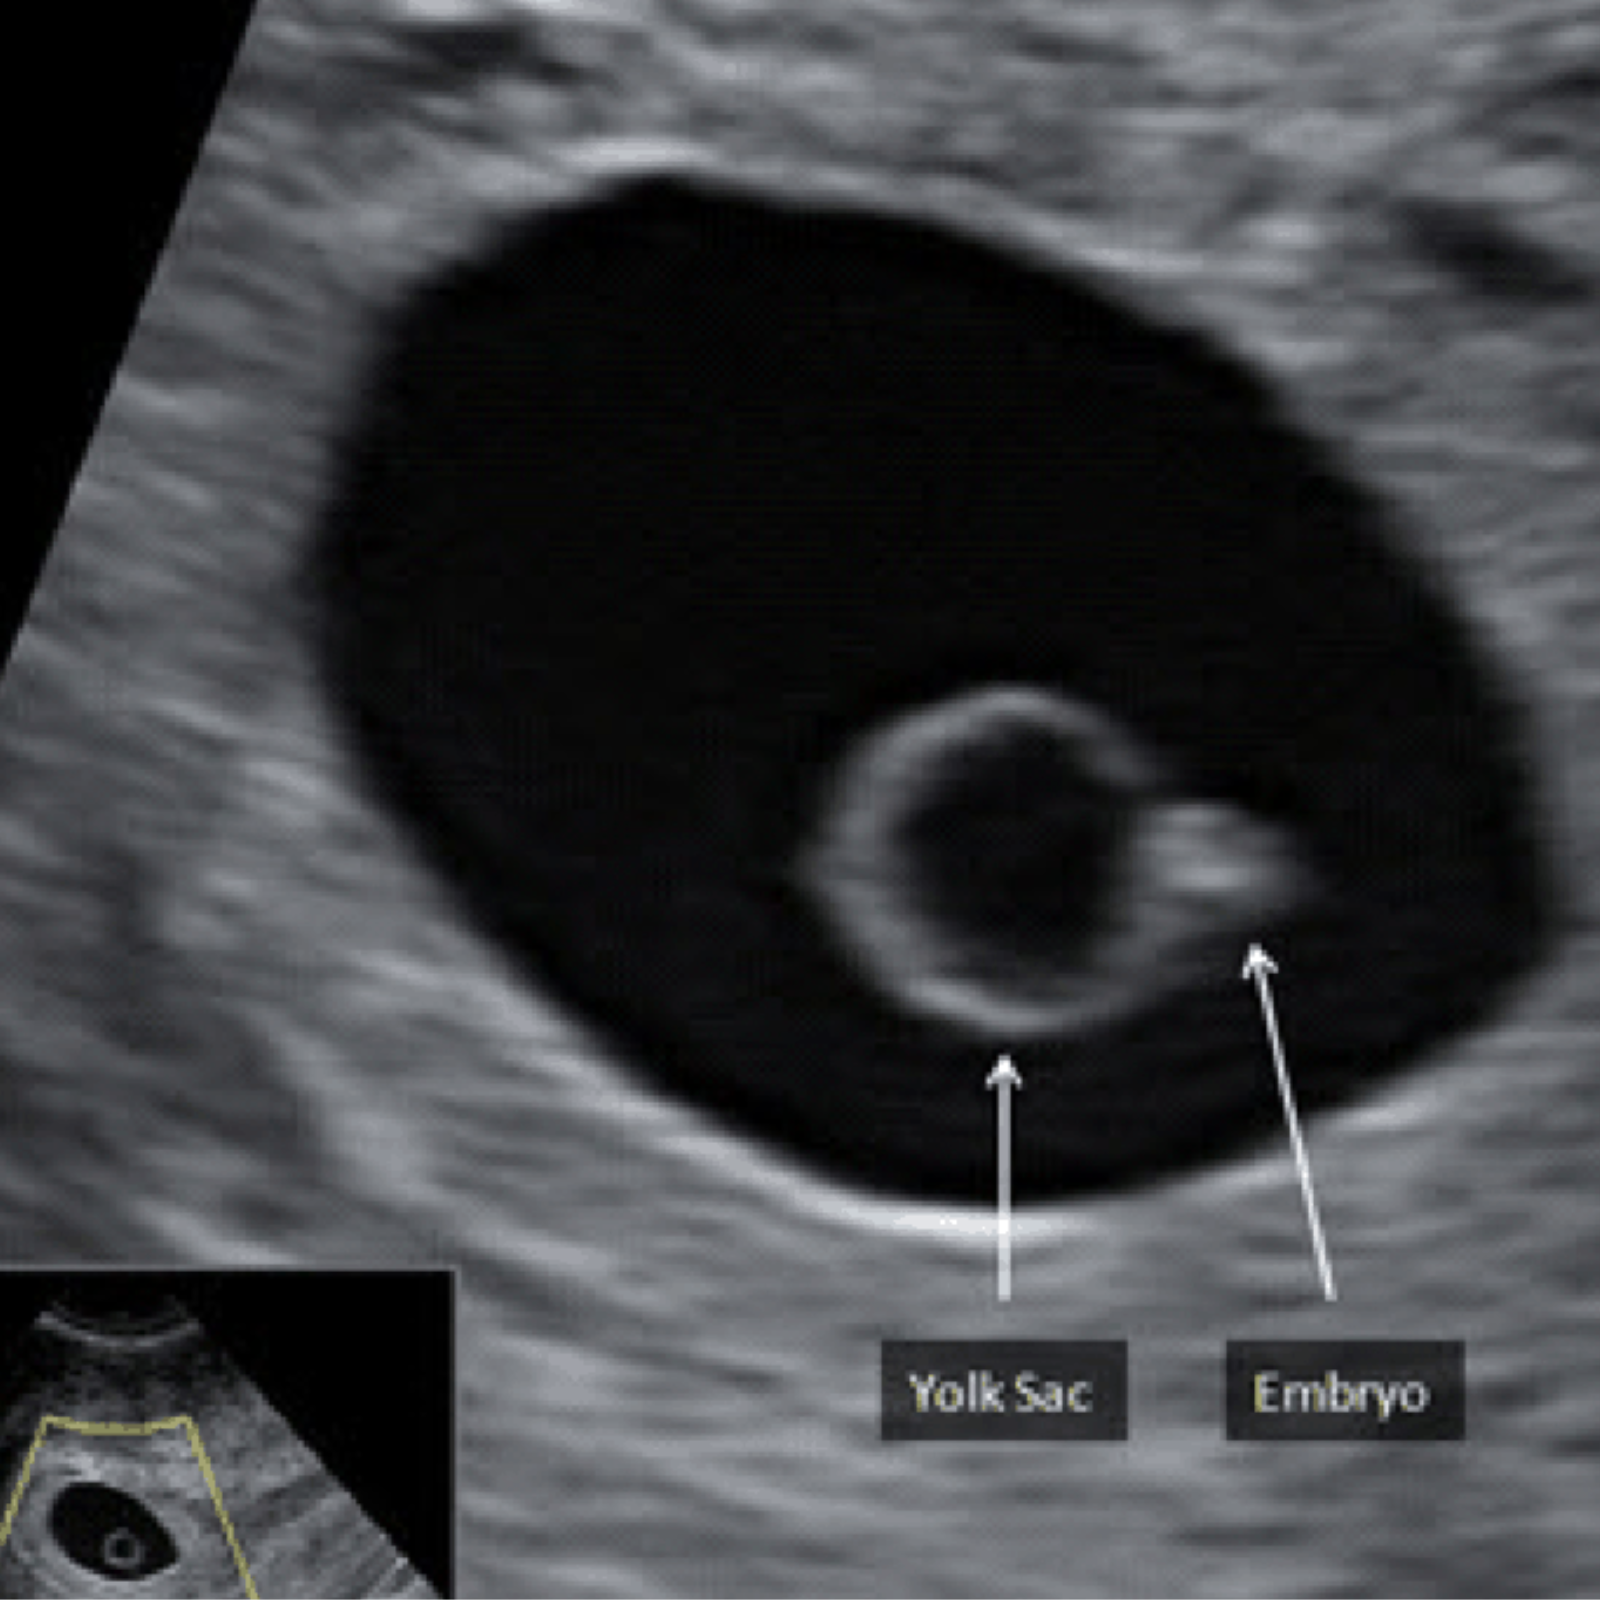

We offer all pregnancy scans, such as early scans, first-trimester Screening scans, Level 2 anomaly scans, routine dating scans, exclusive 3D-4D scans, and obstetric Doppler, using our latest state-of-the-art ultrasound scanning machines. Dr.Saurabh Pandey has extensive specialty interest and experience and has been certified by FMF UK (Fetal Medicine Foundation) to perform level I and II scans. 28